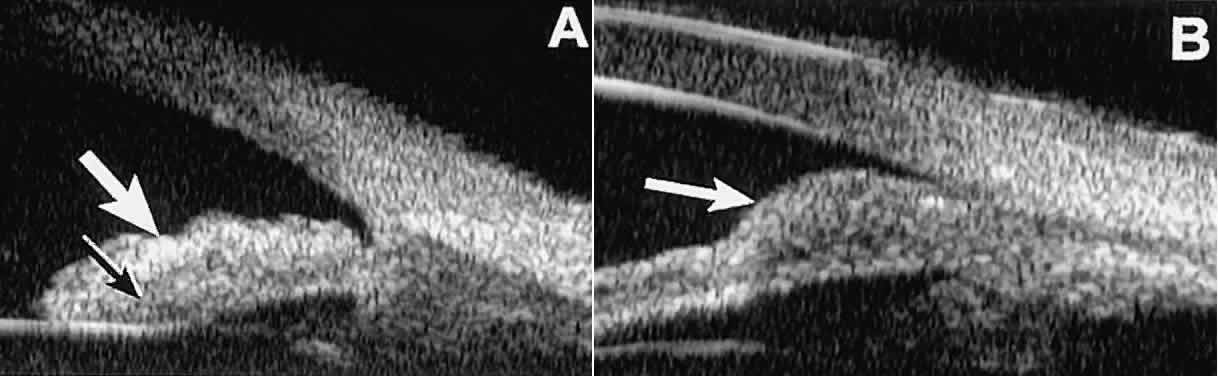

Solid iridociliary tumors present variable internal reflectivity depending on tumor type.14 Most solid lesions that occur on the iris are nevi. Benign nevi of the iris and ciliary body usually appear on UBM as relatively small hyporeflective lesions replacing a part or all of the underlying uveal stroma locally (Fig. 26). Such lesions usually do not destroy the underlying neuroepithelium of the iris or ciliary body, extend intrasclerally, or have prominent intralesional blood vessels.

Fig. 26. UBM features of iris nevi. A. Superficial nevus appears as hyper-reflective layer of iris (white arrow). Normal iris stroma (dark arrow) is more sonolucent. B. Fusiform nevus of peripheral iris occupying full thickness of iris stroma (arrow). Note intact iris pigment epithelium underlying lesion.